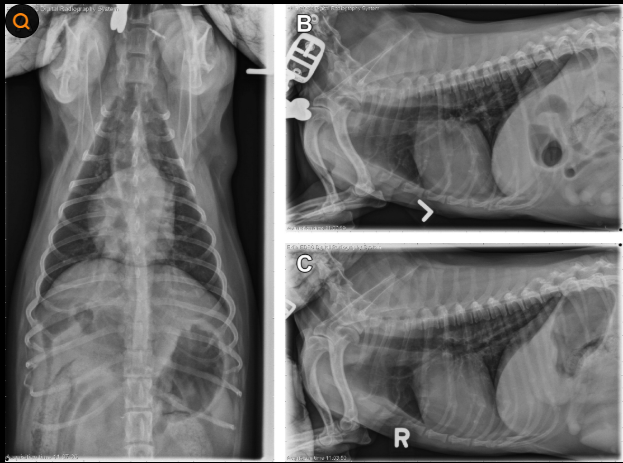

강아지 폐렴 치료의 첫 단계는 정확한 진단입니다. 폐렴은 겉으로 보이는 증상만으로는 확진하기 어렵기 때문에 여러 가지 검사가 필요합니다. 첫 번째 가장 기본적으로 진행되는 검사는 흉부 엑스레이 촬영입니다. 엑스레이를 통해 폐 내부에 염증이나 음영이 있는지 확인하게 되며 폐렴 여부를 판단하는 중요한 검사입니다.

폐렴 치료가 진행되는 동안 강아지 상태가 실제로 좋아지고 있는지 확인하는 것도 매우 중요합니다. 이를 위해 치료 중간이나 퇴원 전에 다시 엑스레이 촬영을 진행하는 경우가 많습니다.

재검사를 통해 폐 염증이 줄어들었는지 확인하고 치료 방향을 조정하게 됩니다. 하지만 이러한 검사 역시 비용이 발생하기 때문에 여러 번 진행될 경우 전체 치료비가 크게 올라갈 수 있습니다. X-Ray 검사,피검사 바이러스 검사 어느것하나 강아지의 현재 건강 상태를 나타내는 지표로 사용 될 자료이기 때문에 상황별로 진행 될수 밖에 없습니다. 하지만 엄청난 비용은 누가 감당해야 할 까요?